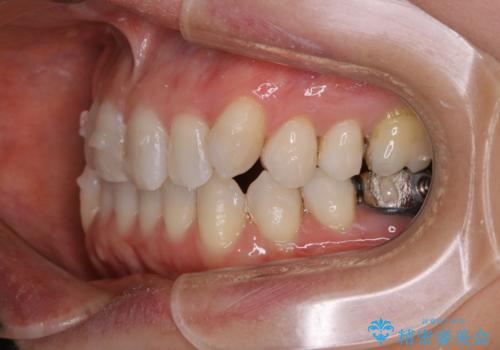

- 右上の小臼歯が二本とも90度捻じれてしまっており、奥歯の噛み合わせに問題が生じていました。

歯を抜いてワイヤー治療を行うという選択肢もありましたが、

奥歯の被せ物の形を適切にすることで非抜歯でも治療が可能であると判断し、

非抜歯、インビザラインでによるマウスピース矯正治療を行うことにいたしました。

今回は右上の奥歯に入っていた銀歯の形が悪く、そのせいで歯を並べるスペースが足りない状態でした。

右上の歯の被せ物を作りなおし、適切な歯の大きさに代えてあげることによってスペースを作りました。

また、それだけではスペースが足りない為右上の奥歯は遠心移動を行っています。